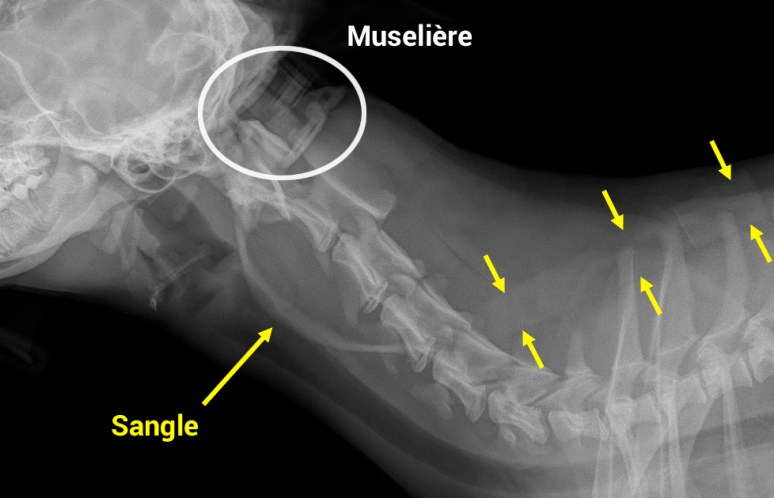

Il s’agit en effet d’une pseudo-lésion créée par la sangle d’une muselière !

Voici d’ailleurs une radiographie prise quelques minutes plus tard sans la muselière: